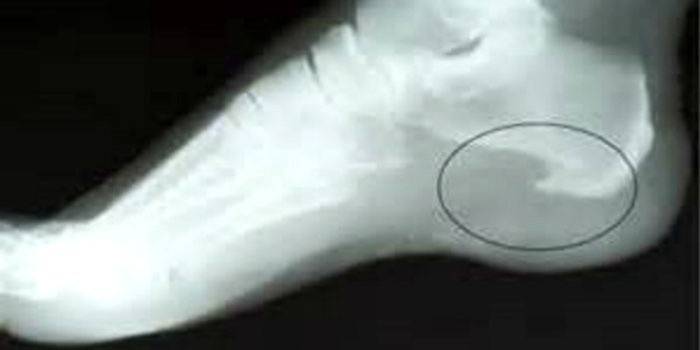

Diagnoza choroby

Zapalenie powięzi podeszwy (kod ICD-10: M77.3) jest chorobą charakteryzującą się stanem zapalnym tkanek miękkich w okolicy pięty, który prowadzi do proliferacji kości w obszarze podeszwy. Na zewnątrz formacja jest podobna do kołka lub kolca, ale tylko lekarz może ustalić dokładną diagnozę. Jej objawy:

- Rentgen stopy. Rentgen z maksymalną dokładnością pokaże, czy istnieje formacja, kolec, który powoduje ból. Jest to niezawodna metoda badania lekarskiego, za pomocą której można potwierdzić diagnozę.